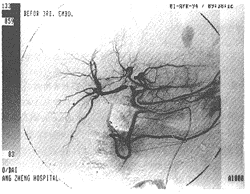

B组在MTX-ms-造影剂混悬液经导管注入肿瘤供应动脉10 min后再次肝动脉造影,大多数能显示肿瘤血管床被完全阻塞,而供应肿瘤血供的动脉分支却保持通畅(见图1,2)。A组在注入碘油时可见肿瘤内的碘油存积,加明胶海绵颗粒栓塞后可使肿瘤血管连同肝动脉的大分支完全阻断,其血供阻断程度似乎更强。

图1 药物微球组病例:肝总动脉DSA检查显示肝右叶上段巨大占位,其内可见众多边缘不规则、扩张迂曲的异常血管增生,周围血管包绕征象明显。

图2 上述病例经肝右动脉用MTX-ms和化疗药物行化疗栓塞治疗,当时肝总动脉DSA复查显示肝右动脉4-5级血管以远的小动脉完全阻塞,肿瘤血管消失,但肝右动脉的大、中分支通畅。

图3 上述病例治疗后4个月行肝总动脉随访DSA检查,肝右叶未见明显异常血管及肿瘤血供;肝内动脉分支显示正常,未见动脉闭塞及侧枝循环产生。